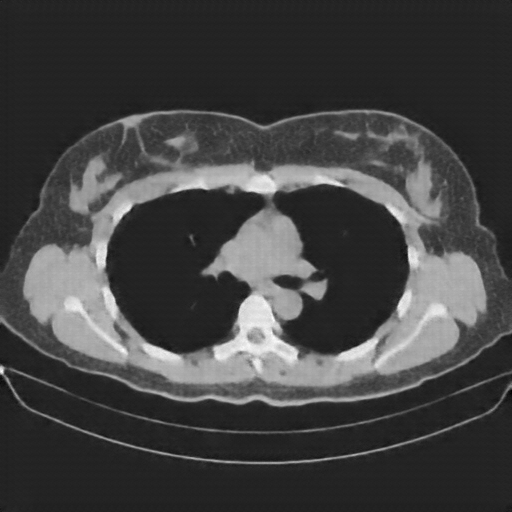

Slice 70 Targeting Evaluation

Slice: Slice_70

Slice Thickness: 1.5mm

Conversion: NATIVE β†’ VENOUS

Original NATIVE CT scan (input)

No window - Raw intensity values